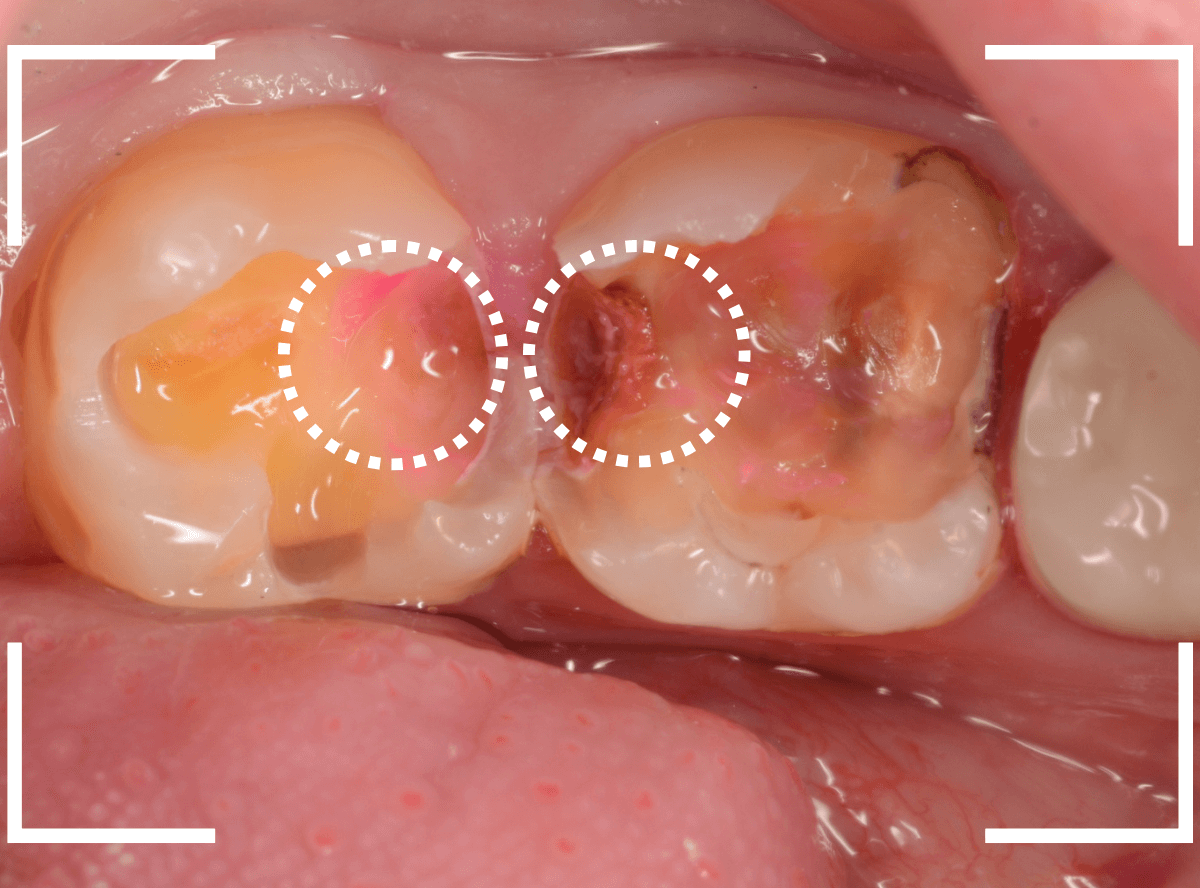

いよいよ神経に近い虫歯まで到達しましたので、手で操作するため、より繊細に虫歯を除去できるエキスカベーターを使用します。

エキスカベーターは先端がスプーン状になっているものや、小さいものなど、様々な形状があり、虫歯の除去の際は、歯を傷つけないように先端が丸みを帯びているスプーンエキスカベーターを使う事が多いです。

使用方法は、スコップで地面を掘るのと同じ要領で、少しでも余分に歯を削らないように、時間をかけて虫歯を除去します。

エキスカベーターを使ってほぼ全ての虫歯を除去したところです。

幸い、神経寸前で虫歯はとどまっていましたが、お薬を詰めて、しばらく経過観察します。